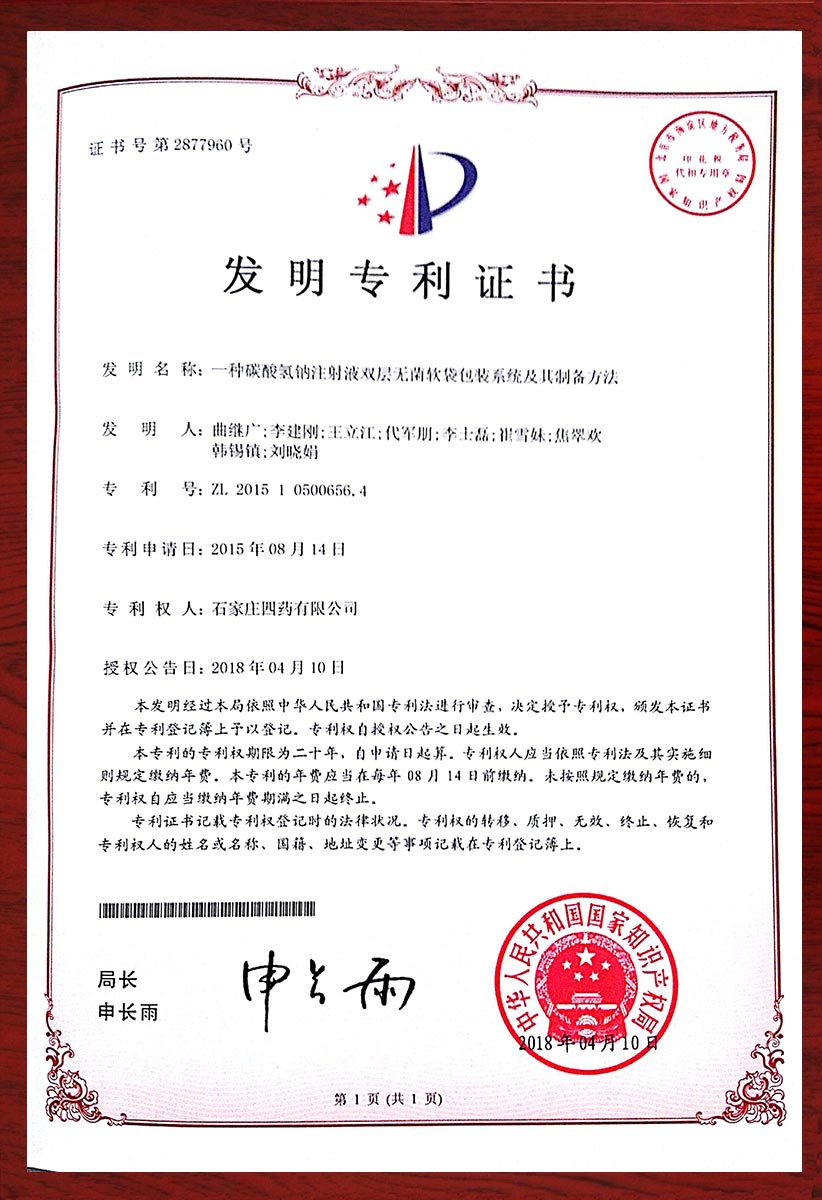

专利证书